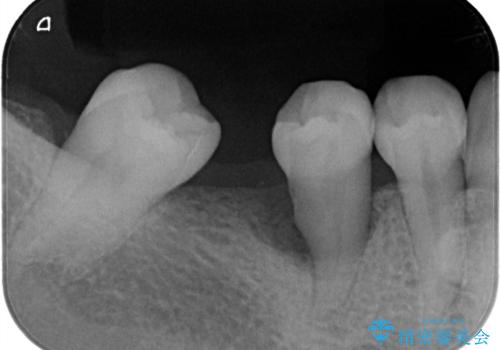

放置したむし歯 抜歯後にインプラントで補綴治療